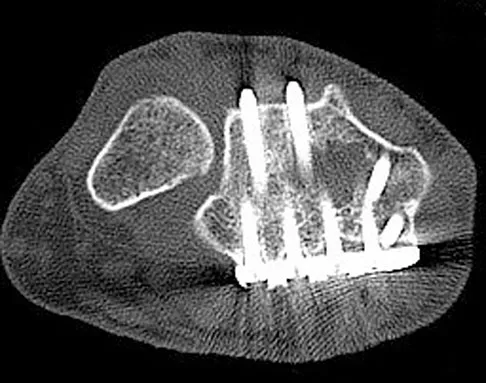

A patient is treated with volar plating for a distal radius fracture. The CT scan shown in Figure 15 is obtained after union of the fracture because the patient reports ongoing symptoms. The prominent hardware is most likely injuring what tendon?

Explanation

Extensor tendon injuries have been reported after volar plating of distal radius fractures. The CT scan shows prominent dorsal hardware a few millimeters ulnar to Lister's tubercle. The second compartment, the ECRL and ECRB, is radial to Lister's tubercle. The ECU runs along the distal ulna. The contents of the fourth dorsal compartment run just ulnar to Lister's tubercle. The EDC tendon is likely irritated in this patient. The EPB runs along the radial border of the radius and is well away from prominent hardware. Benson EC, Decarvalho A, Mikola EA, et al: Two potential causes of EPL rupture after distal radius volar plate fixation. Clin Orthop Relat Res 2006;451:218-222.